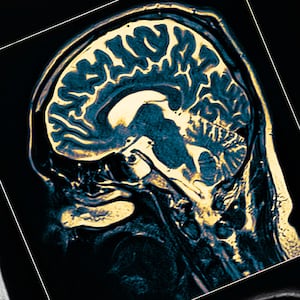

While Parkinson’s is incurable, some of its worst symptoms can be relieved and controlled using medications that increase a patient’s levels of dopamine, a vital neurochemical that plummets due to the destruction of neurons in the brain that make it. A major obstacle to getting effective treatment at the right time is identifying the disease soon enough, before patients experience the symptoms brought on by irreversible neuron loss.